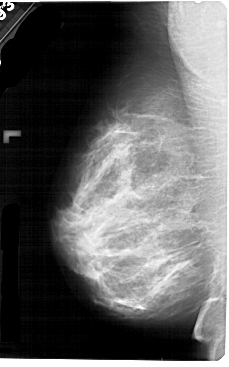

A_1752_1.LEFT_CC

LEFT_CC LINES 5491 PIXELS_PER_LINE 3151 BITS_PER_PIXEL 12 RESOLUTION 43.5 NON_OVERLAY